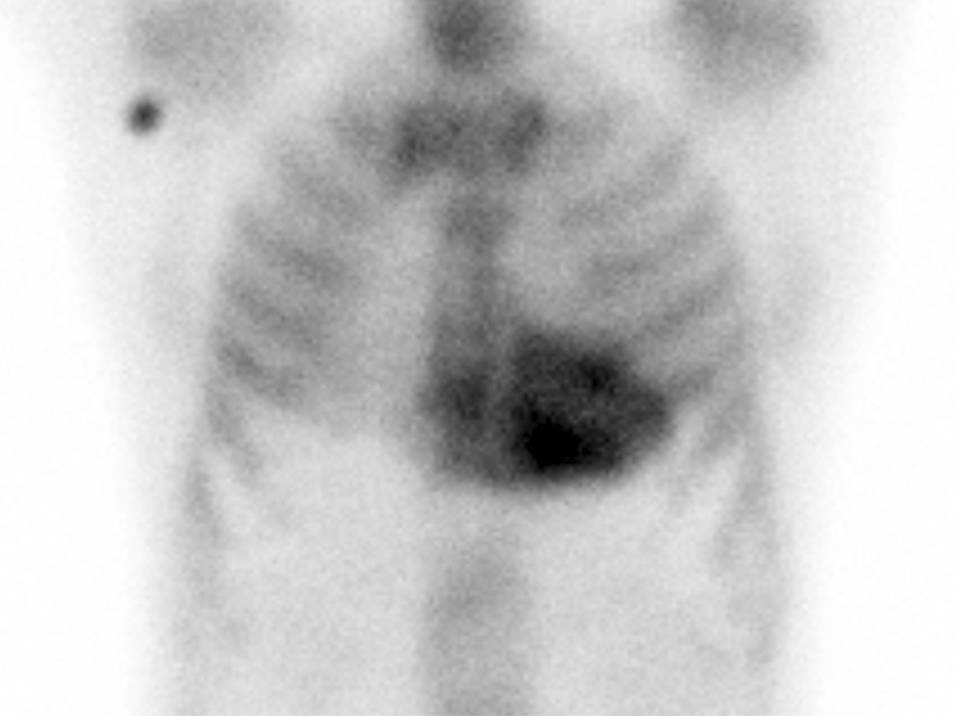

A 65-year-old man was initially admitted to a regional hospital in March 2023 for typical anginal chest pain lasting 3 h. A non-ST elevation acute coronary syndrome was diagnosed and the patient underwent successful percutaneous coronary intervention of a diagonal branch with a drug-eluting stent implantation. His past medical history included arterial hypertension and hyperlipidemia. Of note, there was also a 3-year history of unoperated bilateral carpal tunnel syndrome and 1‑year history of peripheral polyneuropathy. There was no history of spontaneous biceps tendon rupture, lumbar or cervical spinal stenosis. During hospitalization, an echocardiography revealed significant concentric left ventricular (LV) hypertrophy with no regional wall motion abnormalities, preserved LV ejection fraction and grade II diastolic dysfunction. Based on these findings together with the history of abovementioned extracardiac red flags, cardiac amyloidosis was suspected. The use of 99mTc‑3,3‑diphosphono‑1,2‑propanodicarboxylic acid (99mTc-DPD) bone scintigraphy demonstrated high-grade cardiac uptake (Perugini grade 3) (Fig. 1). Plasma cell dyscrasia was excluded by serum free light chain assay and by serum and urine protein electrophoresis with immunofixation. The combination of clearly positive scintigraphy together with negative assessments for monoclonal protein enabled the noninvasive diagnosis of transthyretin cardiac amyloidosis (ATTR-CA) and the patient was referred to our specialized amyloidosis center for further evaluation and management.

Fig. 1

99mTc‑3,3‑diphosphono‑1,2‑propanodicarboxylic acid (99mTc-DPD) bone scintigraphy: anterior planar image demonstrating intense myocardial tracer uptake (Perugini grade 3)